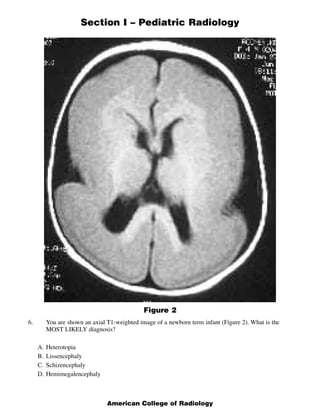

This document contains a multiple choice question and rationales from a pediatric radiology exam. The question shows MRI images of a 22-week fetus and asks for the most likely diagnosis. The rationales eliminate the other answer choices of posterior urethral valves, multicystic dysplastic kidneys, and bilateral ureteropelvic junction obstruction. The correct answer is Autosomal Recessive Polycystic Kidney Disease, as the images show enlarged, fluid-intensity kidneys without urine production, typical of this condition.